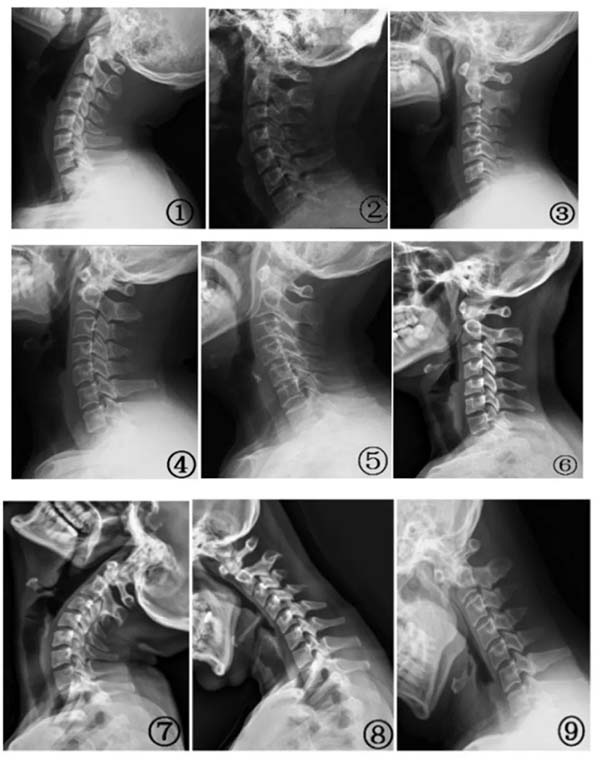

图① 颈椎侧位片;图② 曲度增加;图③ 曲度变直;图④ 曲度变??;图⑤ 弓顶移位;图⑥ 轻度反弓;图⑦ 过伸位颈 4、5 椎体水平位移; 图⑧ 过曲位中段椎体角位移;图⑨ 过曲位中下段椎体角位移和颈 5、6 水平位移。图片来自参考文献[1]